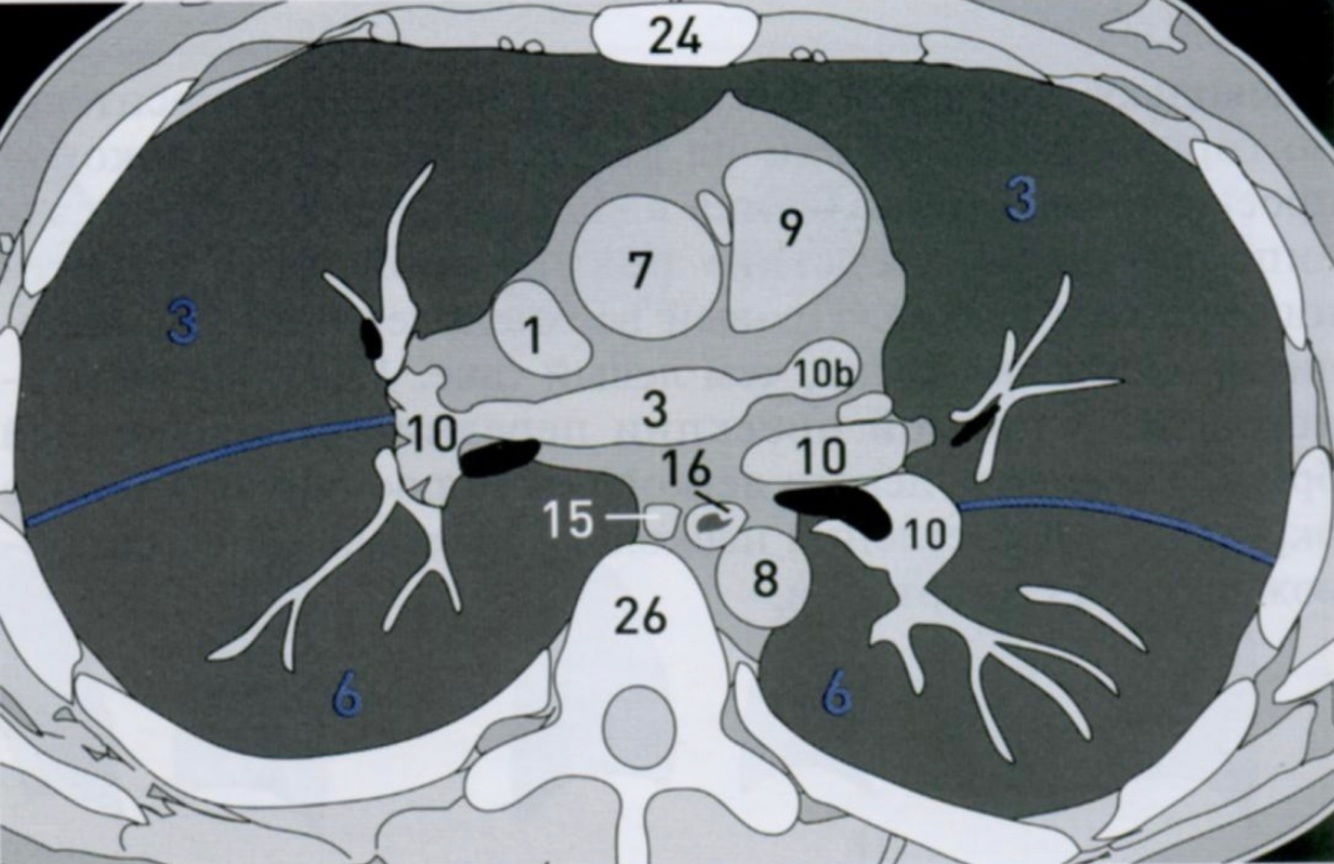

12

Q

КТ грудной клетки №2

Назовите все анатомические структуры, которые Вы знаете, на данном КТ срезе (9).

Найдите грудные позвонки. Затем верхнюю полую вену, восходящую и нисходящую аорту, легочный ствол с легочными артериями, бифуркацию трахеи, непарную вену и пищевод.

A

1 - верхняя полая вена

7 - восходящая аорта

8 - нисходящая аорта

9 - легочный ствол с правой легочной артерией (а) и левой легочной артерией (b)

10 - сосуды

81b - бифуркация

15 - непарная вена

16 - пищевод

Синим цветом отмечены номера сегментов.